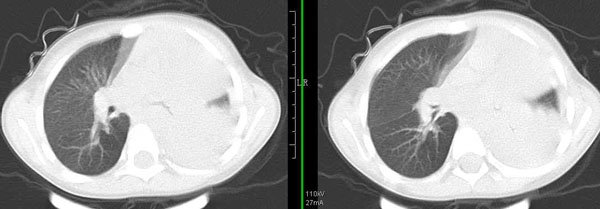

男孩,4岁,发热咳嗽4天。

下面补充ct图片:

左肺门增大,左肺气管阻塞 左肺无肺纹理。右肺代偿性肺气肿。透视图示纵隔摆动。考虑左支气管异物,左肺不张。

此病人是我接手的,发热、咳嗽来做胸透,透视见左侧肺野大部密实,纵隔、心影明显左移,呼吸示纵隔摆动、膈肌矛盾运动(透视下采集了几幅图片),左肺动度明显减弱。询问病人家长,没有吃花生米等呛咳史。由于其影像特征明显,当时诊断:考虑左侧支气管异物并阻塞性肺不张、肺炎。

病人去上级医院支气管镜取出了异物。今天询问上级医院耳鼻喉科主任(是我同学),得知病人异物为胶冻样合并有少许白色粉末,后小儿说晚上喝药片时呛咳过,考虑当时为药片阻塞;另外支气管镜检发现小儿左侧支气管发育略窄,经住院抗炎治疗,现病人基本康复。

多谢各位关注及精彩点评!追踪病人结果时才知道还做过ct检查!对不起!有点晚了,刚刚下载,上传供大家参考!